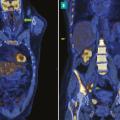

Tomographie par émission de positons : une place centrale dans le bilan et l'évaluation

La tomographie par émission de positons (TEP-scan) est une technique d’imagerie nucléaire fonctionnelle non invasive et désormais largement disponible. Elle est fondée sur l’utilisation d’un radiotraceur radio­actif ciblant un processus biologique, injecté au ­patient, dont la distribution peut ainsi ­être analysée à l’imagerie…